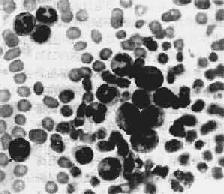

1.周围血像周围血白细胞显著增多,数量正常或减少者少见。CML时白细胞增多尤为明显,多在10万~至80万/μ1之间,少数甚至可超过100万,其中大多数为较成熟的中、晚幼和杆状核粒细胞,早幼粒和原粒细胞很少(图11-7)。嗜碱性和嗜酸性粒细胞也增多。CML时中性粒细胞内碱性磷酸酶常缺如或降低。这点有助于与类白血病反应相区别。CLL血白细胞总数多在3万~10万/μ1之间。血像单一,绝大多数为成熟的小淋巴细胞,只有少数幼淋巴细胞。慢性白血病早期贫血较轻,血小板无明显减少。CML时血小板常增多。晚期有明显贫血和血小板减少。

慢性粒细胞性白血病

图11-7 慢性粒细胞性白血病

周围血内白血病细胞主要为中幼粒细胞